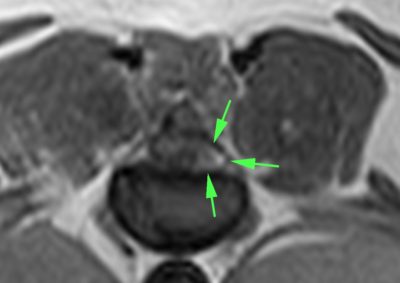

脳神経外科 注意 ボタンをクリックした先に、治療中および手術中の画像が説明で使用されている場合がございます。 そのような画像に弱い方は閲覧なさらないようお願いいたします。 脳神経外科 Ventral Slot 脳神経外科 椎間板ヘルニア 脳神経外科 PLDD 多発性頸部椎間板ヘルニア 脳神経外科 椎間板ヘルニア 脳神経外科 経皮的レーザー椎間板除圧術 PLDD 脳神経外科 椎間板ヘルニア 脳神経外科 環軸椎不安定症に対する環軸固定術 脳神経外科リハビリテーション… 脊髄梗塞 脳神経外科 ベントラルスロット 脳神経外科 ベントラルスロット 脳神経外科 環軸不安定症 脳神経外科内科 Feline Meningoencephalomyelitis of Unknown Origin : 猫の... <1234567> 症例カテゴリー 放射線治療整形外科軟部組織外科脳神経外科内科腫瘍外科救急・集中治療リハビリテーション科腫瘍内科内視鏡科脳神経科呼吸器外科中医・漢方猫の腎移植循環器科